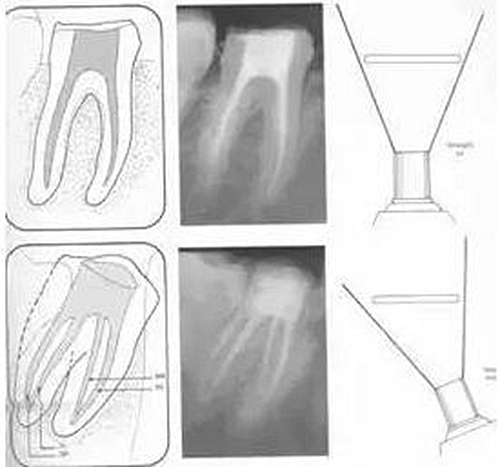

常規(guī)概念的根管預(yù)備后形態(tài)有: ( 1 )便宜形態(tài)( convenience form )。 ( 2 )保持形態(tài)( retention form )。

常規(guī)概念的根管預(yù)備后形態(tài)有:

( 1 )便宜形態(tài)( convenience form )。

( 2 )保持形態(tài)( retention form )

( 3 )抵抗形態(tài)( resistance form )。

1. 便宜形態(tài)

便宜形態(tài)是自切端或咬頜面朝向根尖的直線開擴(kuò)尖錐形態(tài),減少污染物推出根尖孔,方便沖洗、根管充填和側(cè)壁施壓。

2. 保持形態(tài)

保持形態(tài)是根尖狹窄部?jī)?nèi) 1 — 2mm 的一段距離,由擴(kuò)大器回轉(zhuǎn)切割而不貼根管壁提拉切割制成,是擴(kuò)大器的原始形態(tài)(近似平行)。在測(cè)試主牙膠尖時(shí)給測(cè)試者有一個(gè)牽引抵抗 (tugback) 的感覺。

3. 抵抗形態(tài)

抵抗形態(tài)是根管預(yù)備的根尖形態(tài),它是由擴(kuò)大器或根管銼尖端 75 度角自然切割而成。其目的是防止根管充填材超出根尖孔,并且使根尖封閉更加嚴(yán)密。